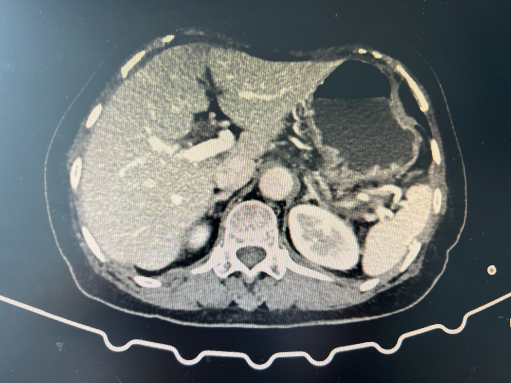

【学科技术】创新手术助力患者康复 —— 我院成功实施首例“腹腔镜脾部分切除术+胆囊切除术”